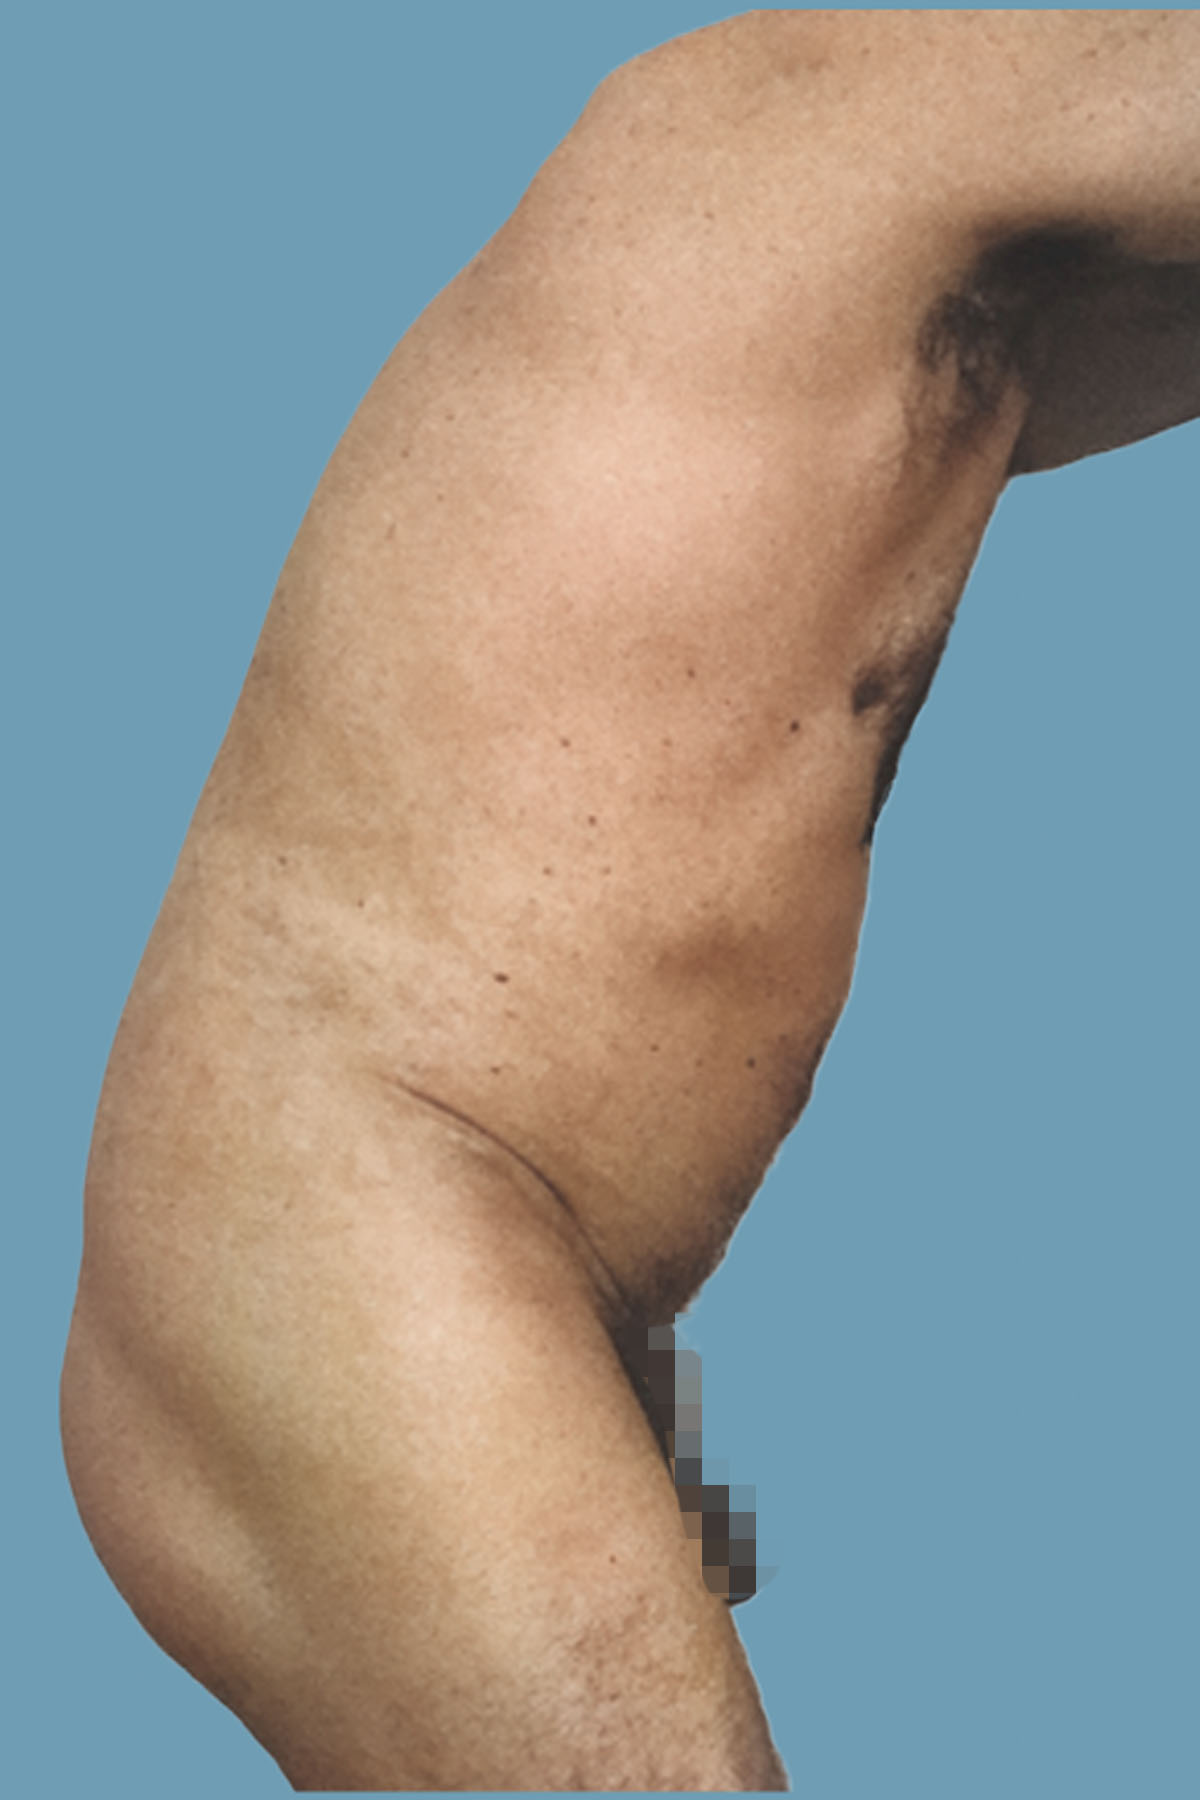

Figure 14. Case 2: Preoperative lateral view shows the global abdominal wall distention.

Figure 15. Case 2: Postoperative lateral view shows the significant clinical improvement in the abdominal wall protuberance. Comparative pre- and postoperative magnetic resonance imaging is shown in Figures 24 and 25.

Figure 16. Case 2: Preoperative view with a hip in flexion. Despite contraction of the abdominal muscles, the distention is unchanged.